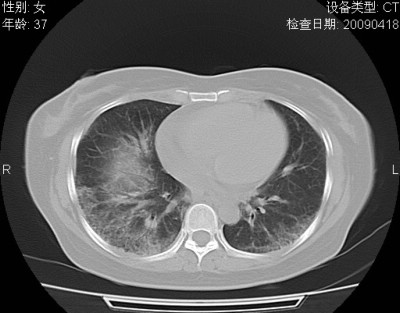

以下是引用随光逐影在2009-4-20 8:03:00的发言:[br]两肺间质性病变(间质性肺炎?特发性肺间质纤维化?)。

以下是引用51736011在2009-4-21 16:24:00的发言:[br]两肺间质性病变(间质性肺炎?特发性肺间质纤维化?)。